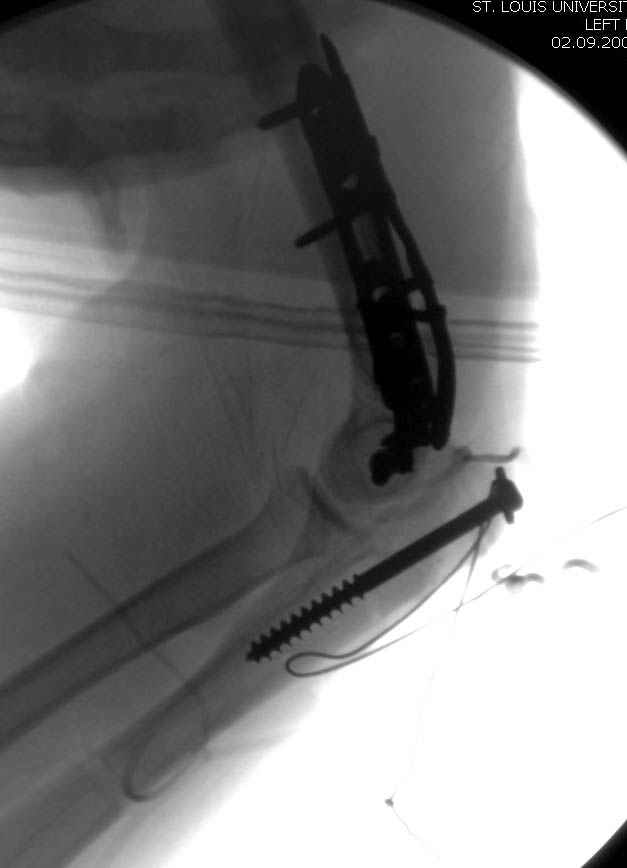

Больному сделали обработку и наложили временный аппарат внешной фиксации плечо-предплечье.

На шестой день сделали открытую репозицию чрезлоктевым доступом двумя locking plate, локтевой нерв был ушибленным, после операции положительная динамика в Flexor Carpi Ulnaris. Фиксацию локтевого отростка произвели tension band technique с дополнительным шурупом.

Этапы операции на снимках....